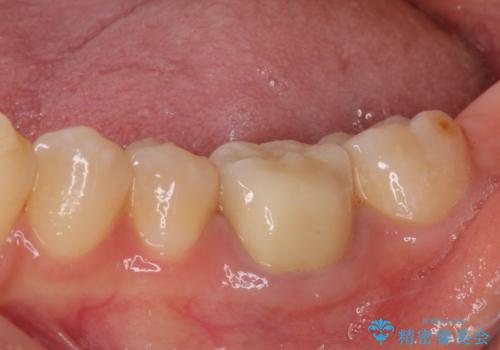

- 奥歯の形が気に入らないとのことで来院された患者様です。

形の変更を希望して、即日装着可能な歯科医院にて治療をしたそうですが、思い通りの形にできなかったとのことでした。

修正可能なように、従来通り技工所に発注して製作するオールセラミッククラウンにて補綴することとしました。

仮歯に置き換えた時点で希望に近い形態とできたので、その形を踏襲してオールセラミッククラウンを製作してもらいました。